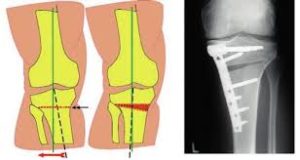

Vervolgens wordt deze breuk gebruikt om de as van het onderste lidmaat te corrigeren tot de gewenste stand. De breuk kan worden opengerekt langs één zijde (=opening wedge osteotomie) of er kan een driehoekige spie of wedge worden verwijderd met nadien sluiten van de breuk (=closing wedge osteotomie).

Na herhaalde controles met het RX toestel wordt de gecreëerde breuk vastgezet met een plaat en schroeven.

Schema van high tibial osteotomie correctie Tomofix plaat voor fixatie na knie-osteotomie